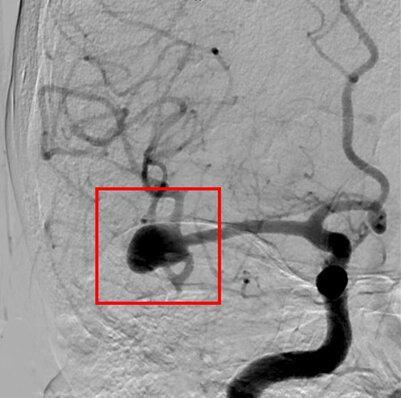

- Angiografia cerebral: exame mais detalhado para visualizar a estrutura dos vasos sanguíneos.

ANGIOGRAFIA CEREBRAL DEMONSTRANDO ANEURISMA CEREBRAL